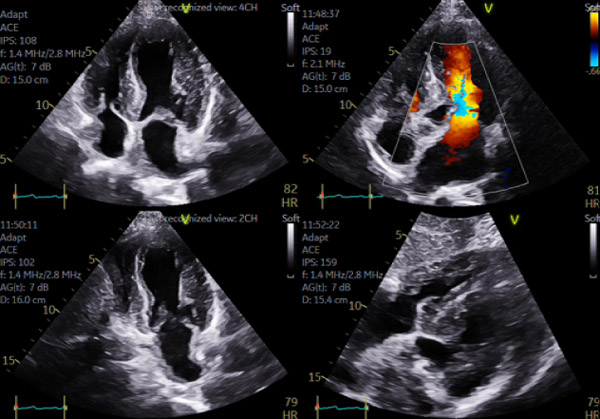

Il faut aussi étudier le ventricule droit, qui est souvent hypertrophié (comme le septum inter atrial et parfois les valves) et les oreillettes qui sont dilatées (mais pas extrêmement alors que leur fonction est souvent effondrée) (Figure 2).

Figure 3 : HVG > 12 mm mais aussi VD en sous-costal. Profil diastolique de type trouble de la relaxation, possible dans l’amylose TTR à un stade pas trop sévère , comme ici où le strain VD est preserve > 23%